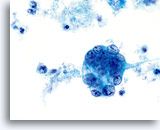

Cytologically, Type I neoplasms show atypical/malignant endometrial cells upon an increased maturation index background. By contrast, Type II neoplasms usually show upon an atrophic background. On ThinPrep samples the endometrial cells will be well preserved and may appear in 3-dimensional crowded groupings of varying sizes as well as small flat sheets containing few cells. The cells usually appear larger than their normal counterpart and the groups have smooth, sometimes scalloped borders giving them a papillary configuration. The cytoplasm is finely to discretely vacuolated and some larger vacuoles can be observed compressing the nucleus to one side of the cell as well as occasionally exhibiting polymorphonuclear cell engulfment. Nuclear features vary dependent upon the grade of the tumor. In general, as the tumor becomes less differentiated, the nucleus tends to round up with an associated gradual increase in nuclear area (µm2), size and number of nucleoli, irregularities in the distribution and coarseness of the chromatin and thickening of the nuclear membranes.

Polymorphonuclear cells may be engulfed in the cytoplasm. 60x

Overall cell size is usually larger than the normal counterpart. 60x

Nuclei “round up” compared to the normal nucleus. 60x

Nuclear membranes may be thickened. 60x

Chromatin may be clumped and irregularly distributed. 60x

Nucleoli are common and vary in frequency, size and number. 60x

Tumor diathesis and single malignant cells may be noted. 60x

Tumor diathesis may be present and appears as a “woven shroud” with a denseness or linear presentation of debris in the center and a frayed or pulled out appearance of the material around the edges of the group. 60x

Endometrial adenocarcinoma 60x